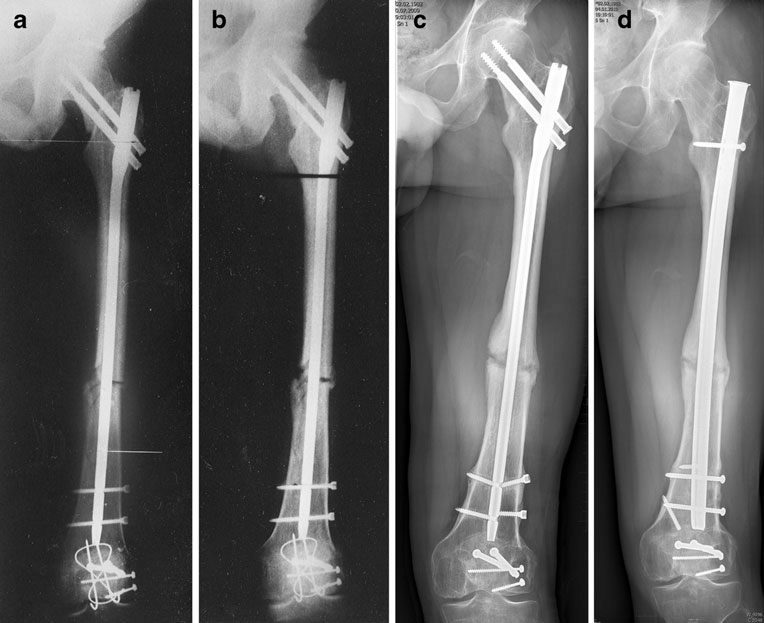

Non Union, Delayed Union, Malunited Fractures

These conditions cause significant morbidity to the patient and pose challenge to treating surgeon. Dr Ankur Rana has vast exposure in treatment of these conditions.

Non-union, delayed union, and malunited fractures can lead to long-term discomfort, limited mobility, and functional impairment, significantly affecting a patient’s quality of life. These complex conditions often require specialized surgical intervention and careful management. At Summit Orthopaedic Hospital, Dr. Ankur Rana brings extensive experience and clinical expertise in treating such challenging cases.